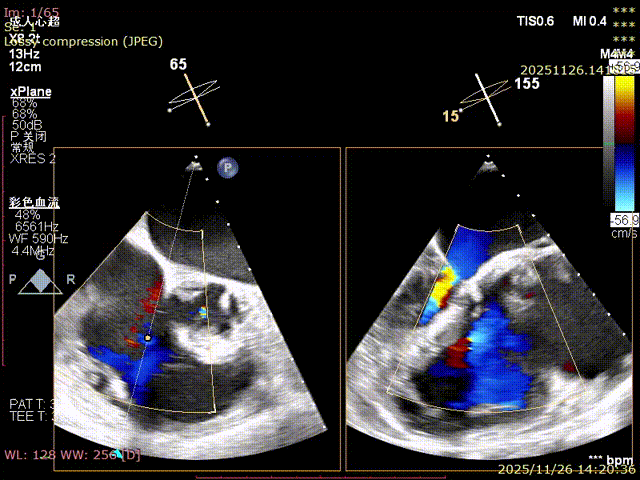

Echocardiography Findings: Severe tricuspid regurgitation (4+), with regurgitation jets primarily located at the postero-septal and central regions. The tricuspid annulus is dilated (annulus diameter: 42 mm).

Mild regurgitation (1+)

For patients with severe functional tricuspid regurgitation, the cardiovascular team developed a personalized strategy through multidisciplinary consultation and innovatively applied the K-Clip® Transcatheter Tricuspid Annuloplasty System. Intraoperatively, transesophageal echocardiography (TEE) combined with digital subtraction angiography (DSA) was used for imaging guidance. A precise access was established via the right internal jugular vein, and the K-Clip® device was delivered to the tricuspid annulus in the right atrium. After multi‑dimensional imaging localization and confirmation, accurate annuloplasty of the posteroseptal commissure (P‑S commissure) was successfully completed.

Immediate postoperative echocardiographic evaluation showed that tricuspid regurgitation was reduced from severe (4+) to mild (1+), with a 30% reduction in annulus area. No adverse events such as atrioventricular block, valve laceration, or cardiac tamponade occurred intraoperatively or postoperatively. Concurrent right coronary angiography confirmed no compression or distortion of the coronary artery course and normal blood flow perfusion. The patient recovered smoothly after the procedure, and right heart failure symptoms were significantly improved at discharge.